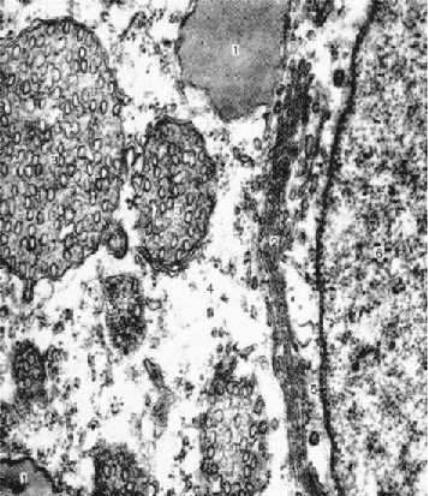

1. Наиболее полно все вышеперечисленные особенности пучковых клеток выявляются при

электронной микроскопии.

На снимке:

липидные капли (1),

гладкая ЭПС (2),

митохондрии (3) с кристами тубулярного типа (выглядят как везикулы).